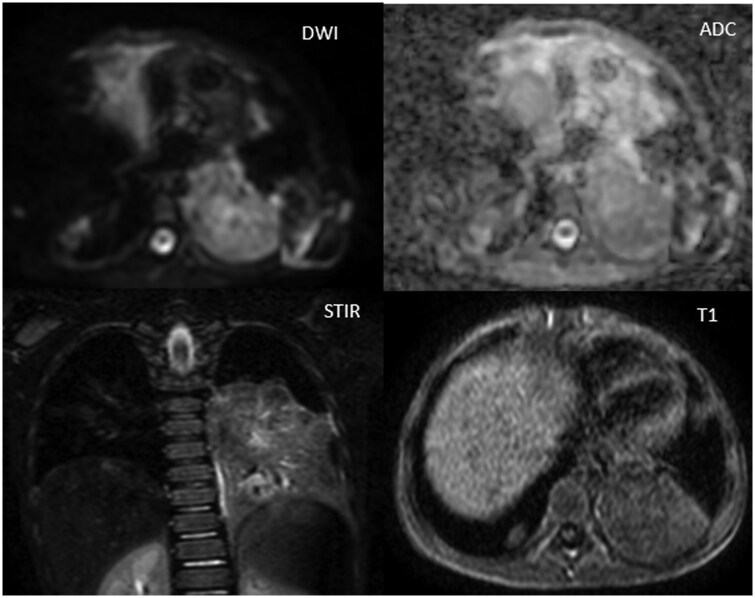

Bronchocentric granulomatosis is a rare form of granulomatous disease characterized by peribronchiolar or peribronchial necrotizing granulomas.1 The imaging findings are non-specific and include nodular or mass-like lesions and pneumonic consolidation.2 We present a case of bronchocentric granulomatosis in a patient with Pre-B-cell acute lymphoblastic leukaemia. The aim of the case report is to make the radiologist aware of this condition and emphasize the importance of multimodality approach which along with clinical findings helps in reaching a diagnosis and managing this rare complication.